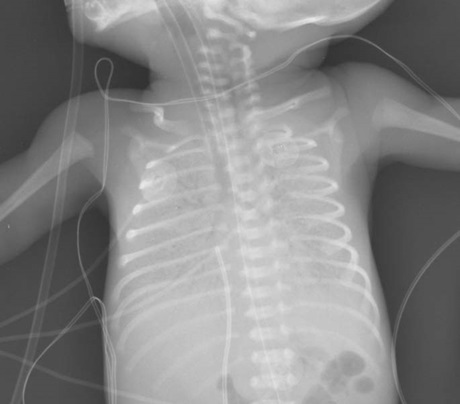

Hội chứng suy hô hấp (RDS), hay còn gọi là bệnh màng trong thường gặp và là nguyên nhân chính gây tử vong ở trẻ non tháng. Các nhà khoa học cho rằng, do thiếu chất hoạt động bề mặt trong phổi (hay còn gọi là chất surfactant) được tạo ra khi em bé đủ tháng trong bụng mẹ và trong thai kỳ, phổi thai nhi chứa nhiều dịch và không hoạt động hô hấp cho đến khi sinh. Để chuẩn bị cho cuộc sống sau khi ra khỏi bụng mẹ, chất surfactant được sản xuất với vai trò làm giảm sức căng bề mặt và khiến phế nang căng phồng, từ đó giảm nguy cơ xẹp phổi. Tỷ lệ mắc RDS tăng khi tuổi thai giảm, trẻ sinh dưới 30 tuần có nguy cơ cao nhất, tuy nhiên có thể chủ động ngăn ngừa hoặc giảm mức độ nghiêm trọng nếu liệu pháp steroid được sử dụng trước sinh cùng biện pháp thở áp lực dương 5, hoặc sử dụng sulfactant ngoại sinh 6.

Hình ảnh X-quang ngực thẳng của một em bé sinh non bị RDS.

Dù được dự phòng, RDS vẫn có thể phát triển và dẫn đến các biến chứng cấp, mạn tính và gây tử vong. Các biến chứng có thể do can thiệp điều trị (đặt catheter động mạch, bổ sung ô xy, thông khí áp lực dương, đặt ống nội khí quản như rò khí phổi, loạn sản phế quản phổi, hẹp động mạch chủ, rò thực quản và hầu họng). Ngoài ra, ống động mạch (PDA) cũng là tình trạng thường gặp ở trẻ sinh non tháng, xảy ra ở khoảng 30% trẻ sơ sinh thể rất nhẹ cân (< 1.500 g). Ống động mạch là ống thông giữa quai động mạch chủ và động mạch phổi, tạo shunt trái phải dẫn đến tăng lưu lượng tuần hoàn phổi và giảm tưới máu lưu thông toàn thân. Hậu quả của PDA phụ thuộc vào kích thước của shunt và phản ứng của tim phổi với shunt (nếu shunt lớn có thể xuất hiện các triệu chứng như ngưng thở, suy hô hấp hoặc suy tim). Trẻ sinh non có shunt từ trái sang phải từ trung bình đến lớn có tỷ lệ tử vong cao hơn hẳn so với trẻ không có PDA, đặc biệt ở nhóm trẻ sinh non dưới 28 tuần.